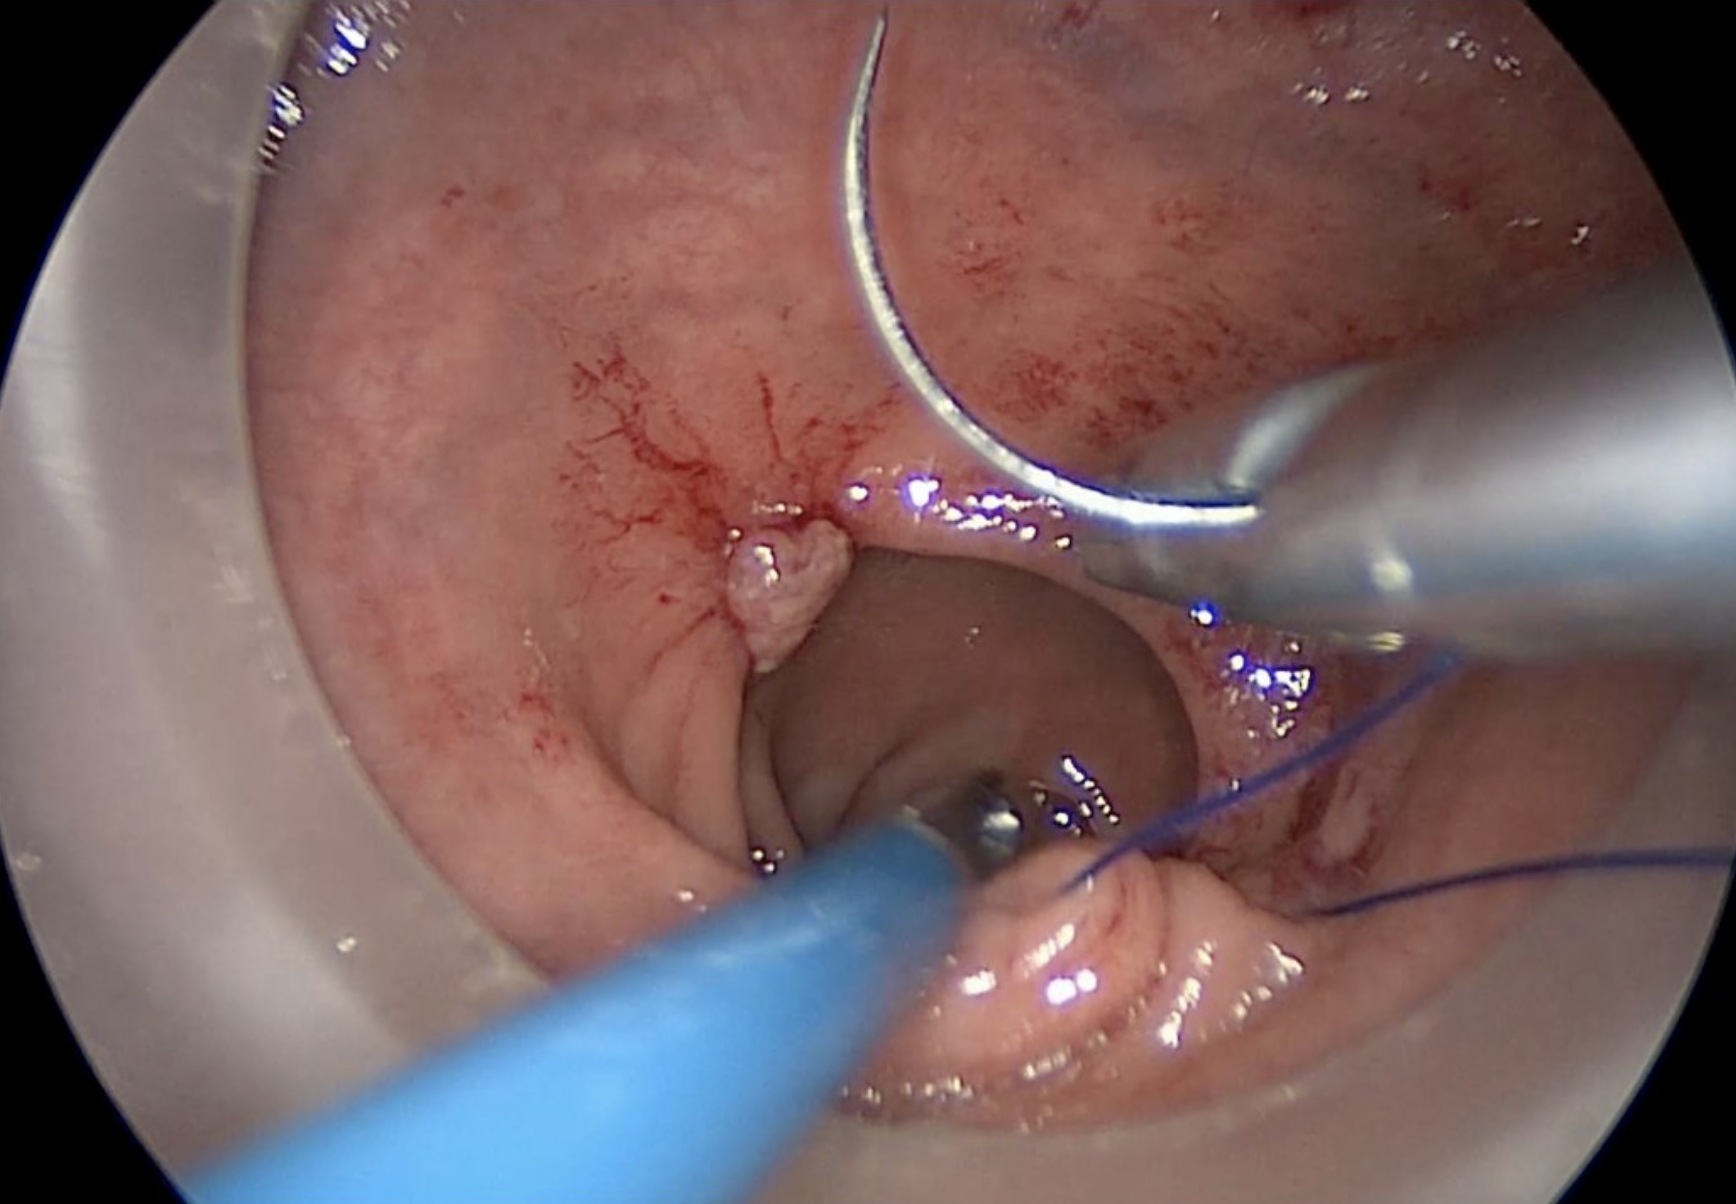

The placement of an 0 Prolene purse-string suture is the initial step of the transanal technique. It is placed from within the rectum to seal the lumen below the tumour, and to mark the distal resection margin.

Placement of rectal pursestring. Note the dotted line indicating the accurate circumferential placement of the stitch below the lower edge of the tumour.